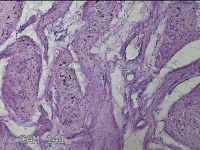

子宫体肌瘤结节

性别

女

年龄

32岁

临床诊断

子宫肌瘤 疤痕子宫

一般病史

发现子宫肌瘤数月余。

标本名称

大体所见

灰白色圆柱形条索状组织10x7.5x1.8㎝一堆,切面均为灰白色结节状或编织状,质中。